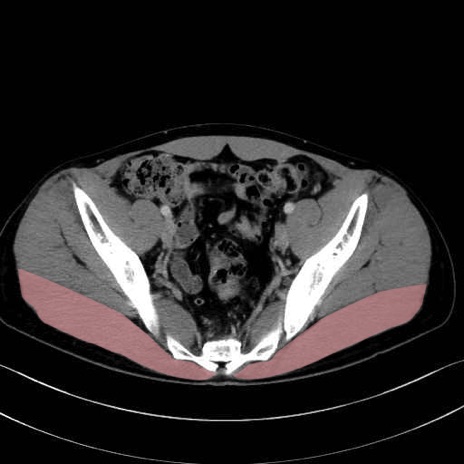

大殿筋 (Gluteus maximus)